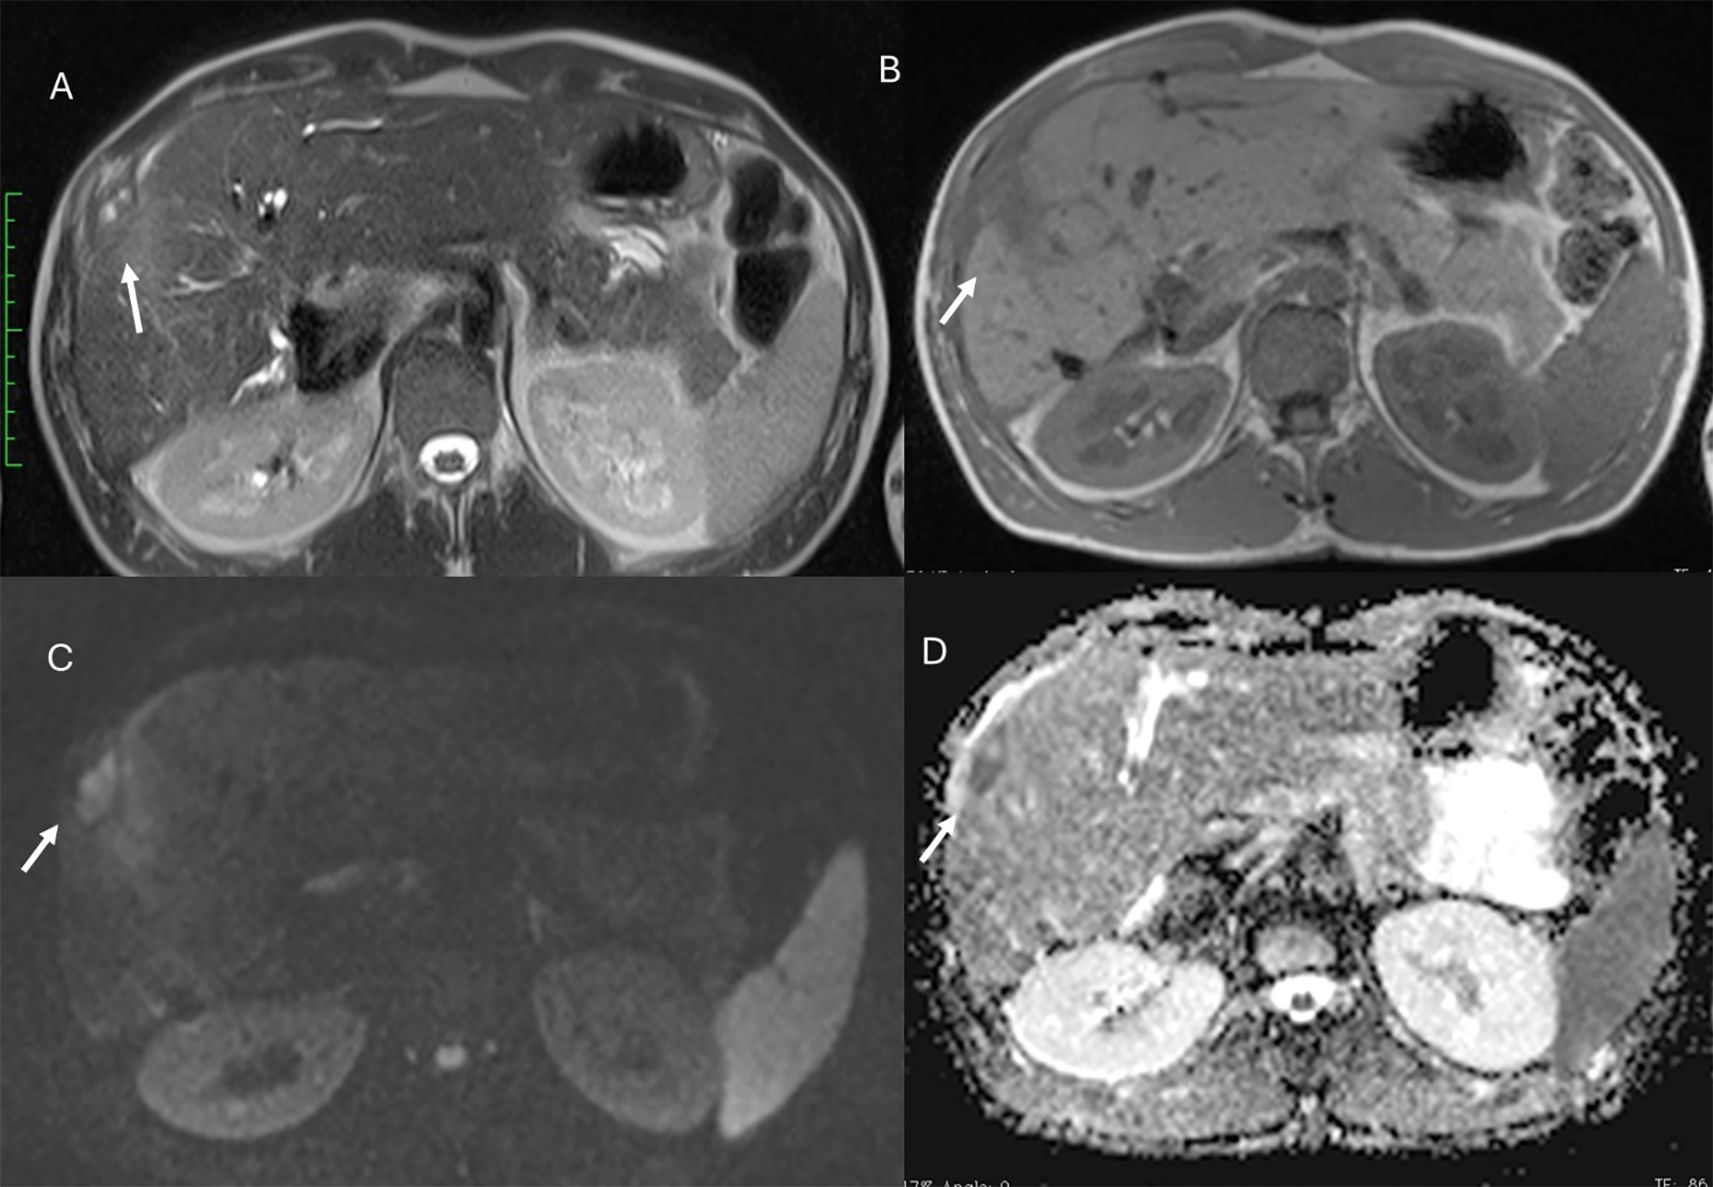

Figure 9. MRI of liver abscess after surgical resection. The lesion (arrows) shows hyperintense signal in T2-W sequence (A), hypointense signal in T1-W sequence (B), restricted diffusion on b = 800 s/mm² (C), and hypointense signal on ADC map (D). This demonstrates that a benign lesion can also show restricted signal and hypointensity on ADC maps.

Figure 10. MRI assessment of residual disease after surgical resection. The lesion shows similar features to the patient in Figure 9, with hyperintense signal in T2-W sequence (A), hypointense signal in T1-W out-of-phase sequence (B), restricted diffusion on b = 800 s/mm² (C), and hypointense signal on ADC map (D). In this case, DWI is suggestive of residual lesion.